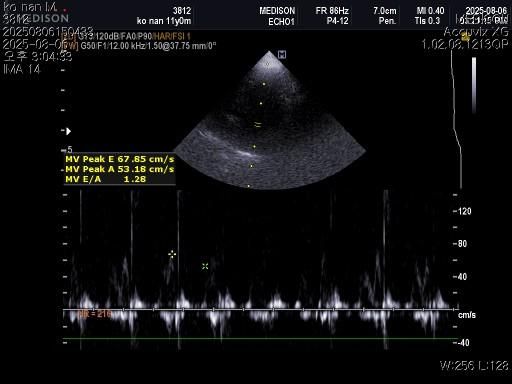

1) 혈액검사와 엑스레이 그리고 초음파상 혈뇨의 원인이 나타나지가 않는지 궁금합니다.

2) 그리고 전립선 비대가 있는지도 없는지 여부가 궁금합니다.